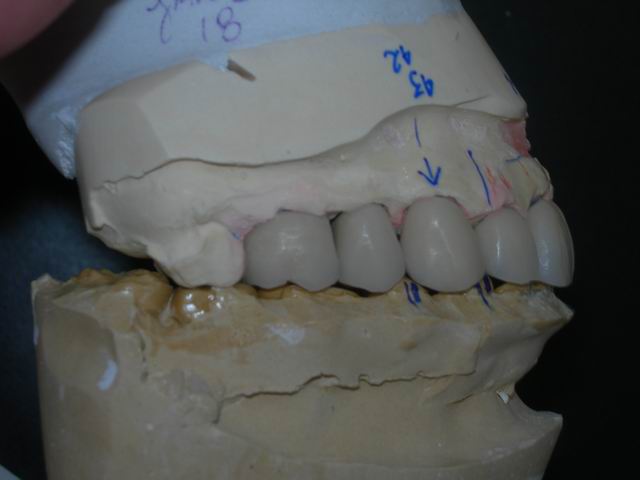

Modelo de trabalho troquelado sobre o qual se confeccionam os "dentes artificiais" sob medida